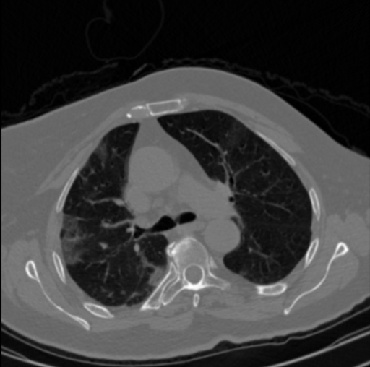

Early and reliable COVID-19 diagnosis based on chest 3-D CT scans can assist medical specialists in vital circumstances. Deep learning methodologies constitute a main approach for chest CT scan analysis and disease prediction. However, large annotated databases are necessary for developing deep learning models that are able to provide COVID-19 diagnosis across various medical environments in different countries. Due to privacy issues, publicly available COVID-19 CT datasets are highly difficult to obtain, which hinders the research and development of AI-enabled diagnosis methods of COVID-19 based on CT scans. In this paper we present the COV19-CT-DB database which is annotated for COVID-19, consisting of about 5,000 3-D CT scans, We have split the database in training, validation and test datasets. The former two datasets can be used for training and validation of machine learning models, while the latter will be used for evaluation of the developed models. We also present a deep learning approach, based on a CNN-RNN network and report its performance on the COVID19-CT-DB database.